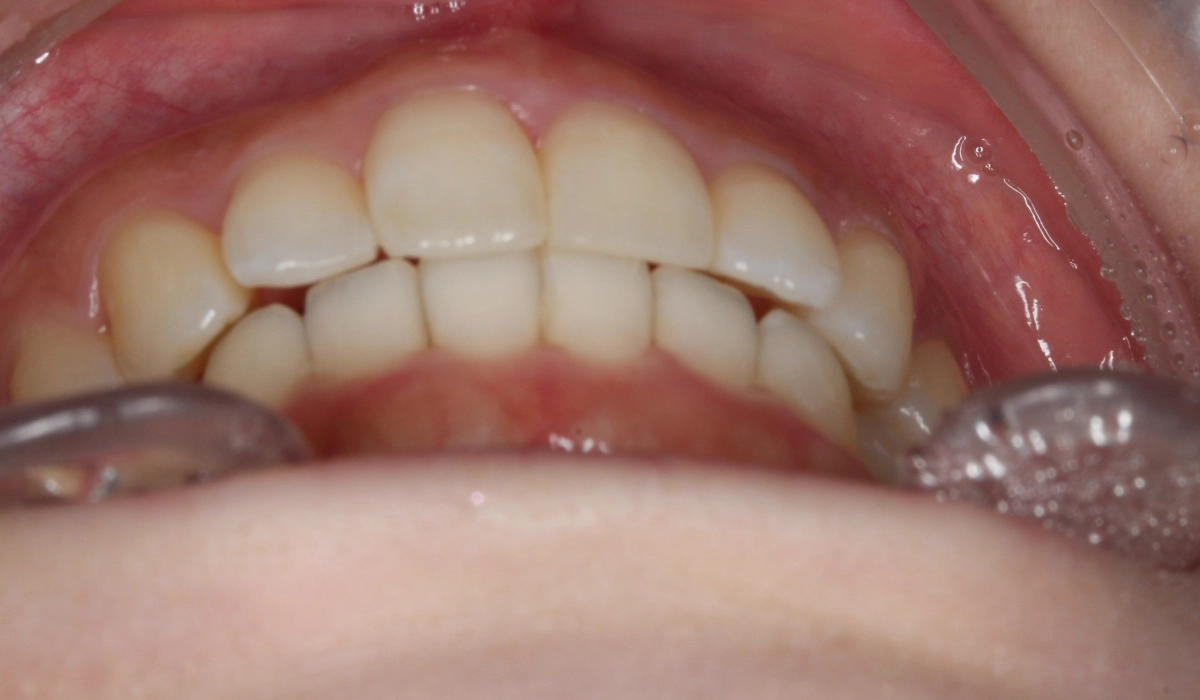

術後:前歯部

術後:正面

術後:右側

術後:左側